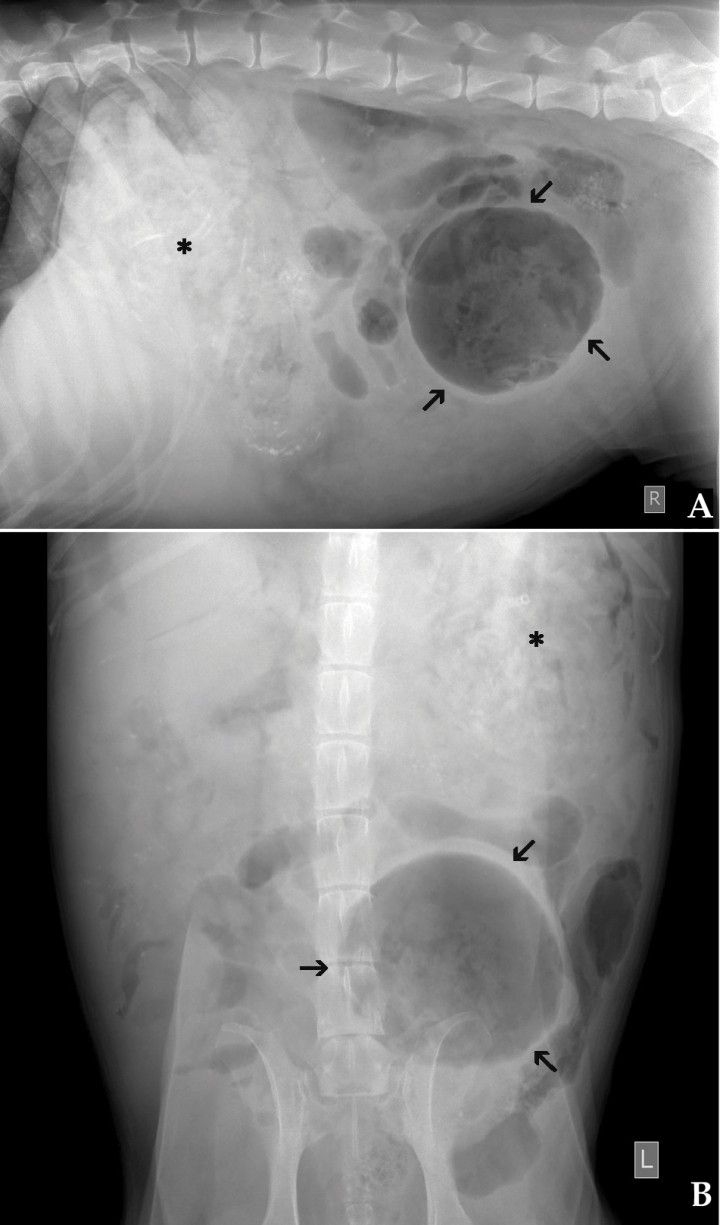

Se presenta en urgencias un Golden Retriever, hembra, castrada de 9 años de edad y 30 kg de peso que había sido atropellada por un coche. A la exploración física se observaron las mucosas pálidas, taquicardia (160 l.p.m.), taquipnea (60 r.p.m.), pulso débil, distensión abdominal y debilidad del tercio posterior. A la palpación del abdomen se evidenció la presencia de una masa situada a nivel medio-caudal, que al percutirla emitía un sonido timpánico y provocaba malestar en el animal. Tras estabilizar al paciente mediante la administración de fluidoterapia, oxigenoterapia y analgesia se realizaron radiografías de tórax y de abdomen (Figs. 1A y B).

<p>(A) Imagen radiografica lateral derecha y (B) ventrodorsal de la cavidad abdominal.</p>

(A) Imagen radiografica lateral derecha y (B) ventrodorsal de la cavidad abdominal.

En las radiografías torácicas no se observó ninguna alteración evidente. En las radiografías de la cavidad abdominal (Figs. 2A y 2B) se apreció una pérdida de visualización de serosas de forma generalizada, más acentuada en la zona ventral derecha, así como presencia de gas libre. En la zona caudal izquierda se observó una estructura cavitaria con bordes bien definidos, de aproximadamente la longitud de tres cuerpos vertebrales lumbares (flechas de las Figs. 2A y 2B), que desplazaba algunas asas de intestino delgado hacia dorsal y craneal, y el colon descendente hacia la izquierda. En el interior de la estructura cavitaria también se apreciaba una opacidad tejido blando con áreas radiotransparentes.

<p>Mismas imágenes que la Fig 1. En ambas imágenes se aprecia pérdida de visualización de las serosas y presencia de gas libre en la zona ventral derecha. En abdomen caudal se observa una estructura cavitaria con bordes bien definidos (flechas) que desplaza dorsal y ventralmente a asas de intestino delgado y hacia la izquierda al colon. El estómago se encuentra distendido y con contenido heterogéneo, con cuerpos extraños de opacidad hueso (asterisco).</p>

Mismas imágenes que la Fig 1. En ambas imágenes se aprecia pérdida de visualización de las serosas y presencia de gas libre en la zona ventral derecha. En abdomen caudal se observa una estructura cavitaria con bordes bien definidos (flechas) que desplaza dorsal y ventralmente a asas de intestino delgado y hacia la izquierda al colon. El estómago se encuentra distendido y con contenido heterogéneo, con cuerpos extraños de opacidad hueso (asterisco).

El hígado estaba ligeramente aumentado de tamaño, con bordes redondeados y desplazando caudalmente el eje gástrico. El estómago presentaba un contenido heterogéneo y pequeños cuerpos extraños de opacidad hueso (asterisco de las Figs. 2A y B)